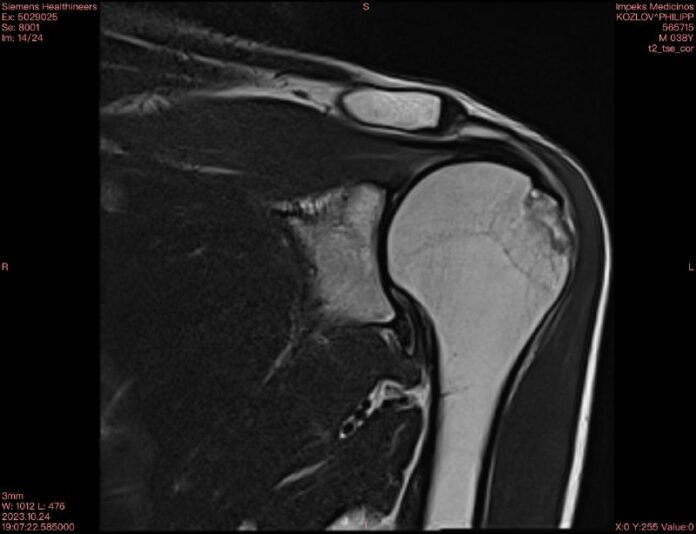

Продолжая выкручивать левую руку, молодого человека подняли на ноги и в полусогнутом состоянии повели к подъезду для обыска в его квартире. На днях Козлову пришли результаты МРТ: перелом плечевого сустава. Он рассказал, что рука не перестает болеть и с трудом поднимается уже третий месяц.